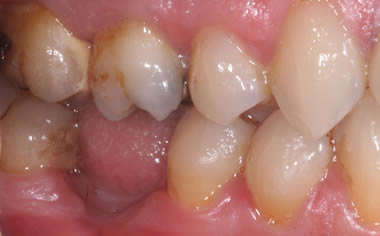

More back teeth replaced by dental implants

Case Four (4 images)